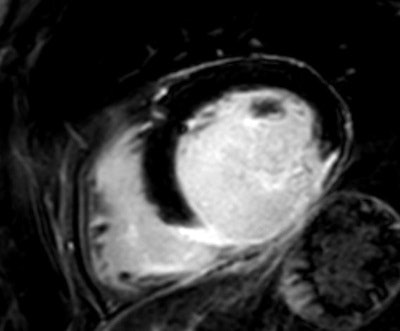

A 59- year-old man with acute myocardial infarction: late enhancement inferior and inferolateral, basal to apical, accompanied by a slight contrast substance enrichment of the pericardium.In my practice I have certainly gained more knowledge in working with CMR, and I continue to get more ideas about how to use it to answer specific questions, such as late enhancement for detecting scar tissue, T2-weighted imaging for edema, short axis view, and aortic and pulmonary flow for precise volumetry.